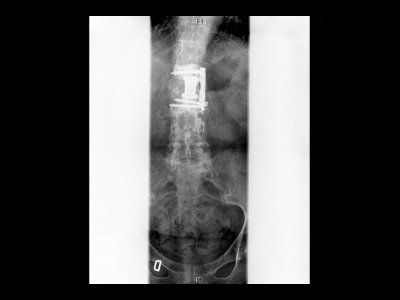

Espondilolistesis